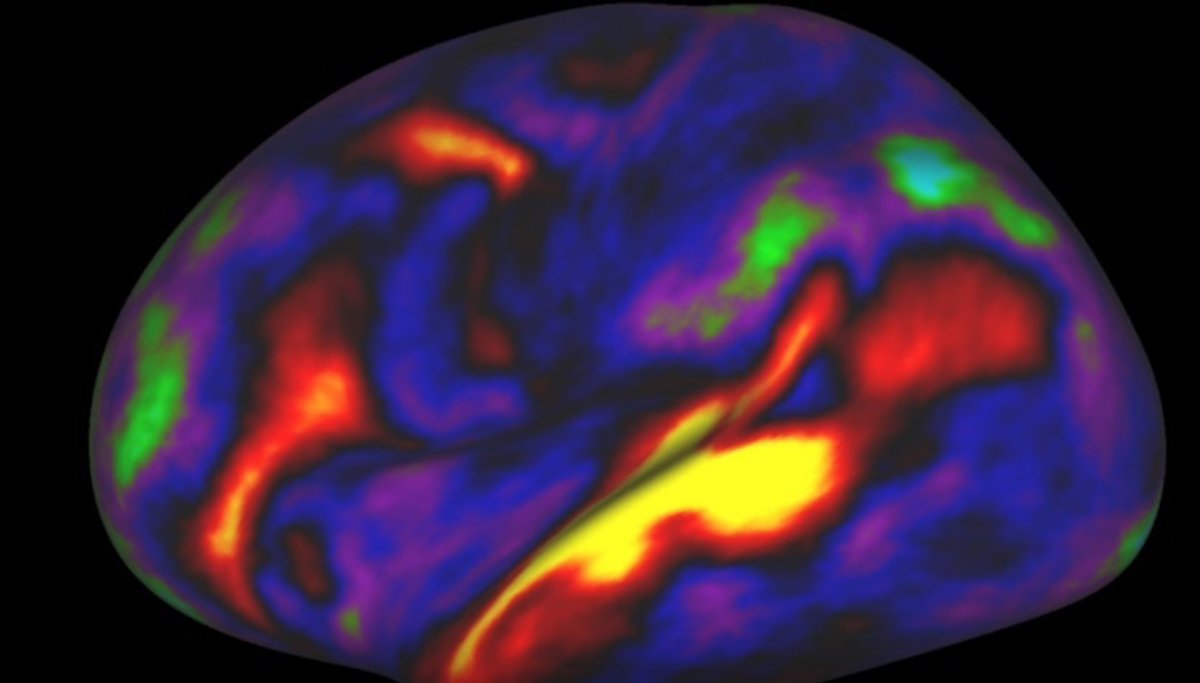

Mapa del cerebro

El desarrollo de un mapa preciso y de alta resolución de la arquitectura microestructural (o estructura local), la conectividad y la función del cerebro humano ha sido, durante mucho tiempo, un objetivo difícil de alcanzar de la neurociencia, debido a problemas técnicos.

Pero ahora, investigadores de la Universidad de Washington (San Luis, EE UU) y de otras instituciones estadounidenses han realizado un mapa de 97 nuevas áreas de la corteza cerebral humana, además de confirmar otras 83 que ya se conocían previamente.

El trabajo ha dividido cada hemisferio del cerebro en 180 áreas corticales específicas -97 de ellas de nueva descripción-. Además, los investigadores han utilizado una técnica de aprendizaje automático para validar su mapa en un grupo independiente de otros 210 participantes adicionales. El estudio ha identificado con precisión estas regiones en los nuevos voluntarios, pese a la variabilidad individual.